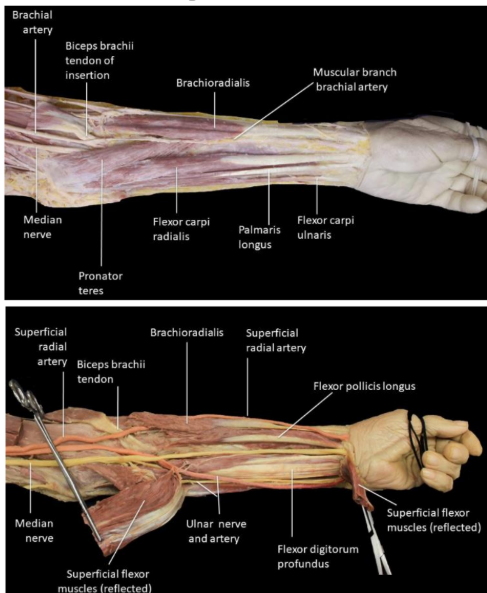

Cubital fossa

Triangular hollow region situated in front of the elbow joint

Boundaries

Laterally- medial border of brachioradialis

Medially- lateral border of pronator teres

Base- directed upwards and formed by an imaginary line joining two epicondyles

Apex- directed downwards and formed by overlapping of medial and lateral boundaries

Roof- skin, superficial fascia with its contents, deep fascia

Floor- brachialis above and supinator below

Contents

Median nerve

Tendon of biceps brachii

Termination of brachial artery

Ulnar artery

Radial artery

Radial nerve

Forearm

Contains anterior and posterior compartment

Anterior compartment

Superficial- pronator teres, flexor carpi radialis, palmaris longus, flexor digitorum superficialis, flexor carpi ulnaris

Deep- flexor policis longus, flexor digitorum profundii, pronator quadratus

Radial and ulnar arteries

Median, ulnar and radial nerves